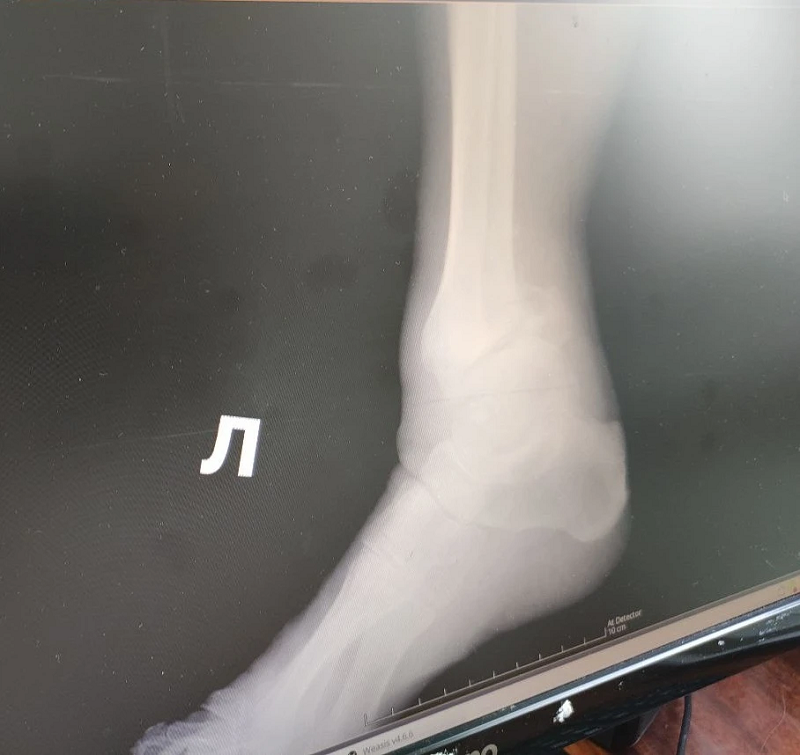

Фото ЯММЦ ФМБА России